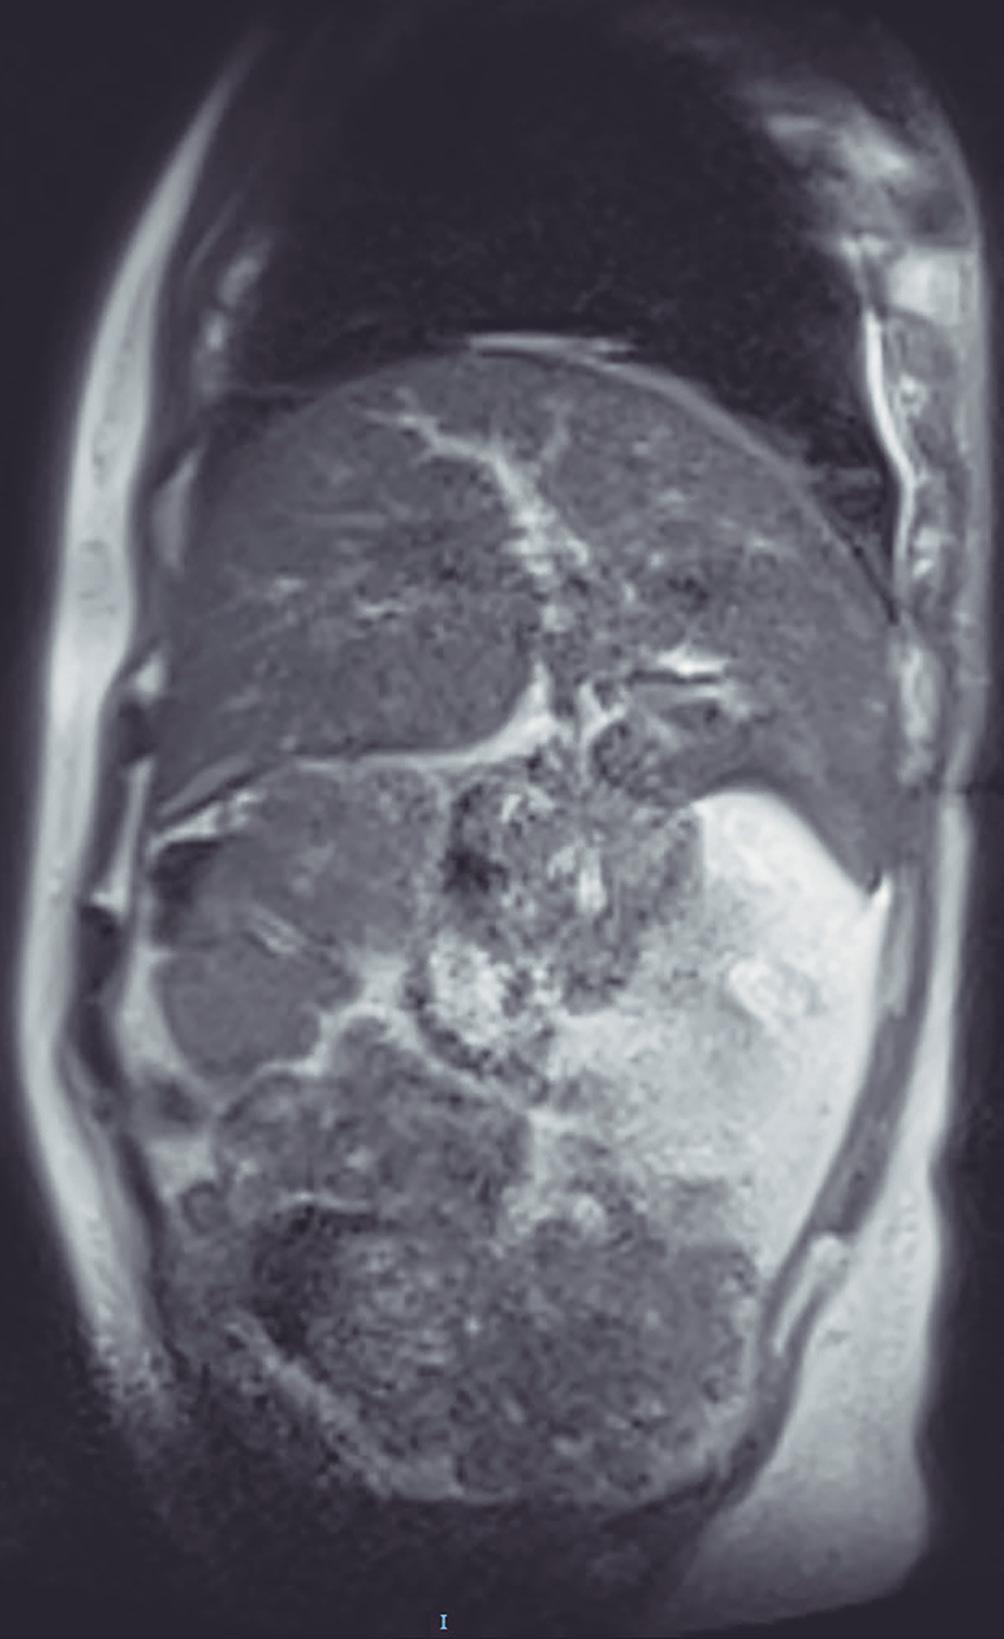

Obstrucción intestinal duodenal en una adolescente femenina

Omar Daniel Cortés-Enríquez, Claudia Vanessa Tapia-Fonseca, Julio César Riojas-Robles, Laura Patricia Raya-Garza, Karla Guadalupe Rodríguez-Alvarado